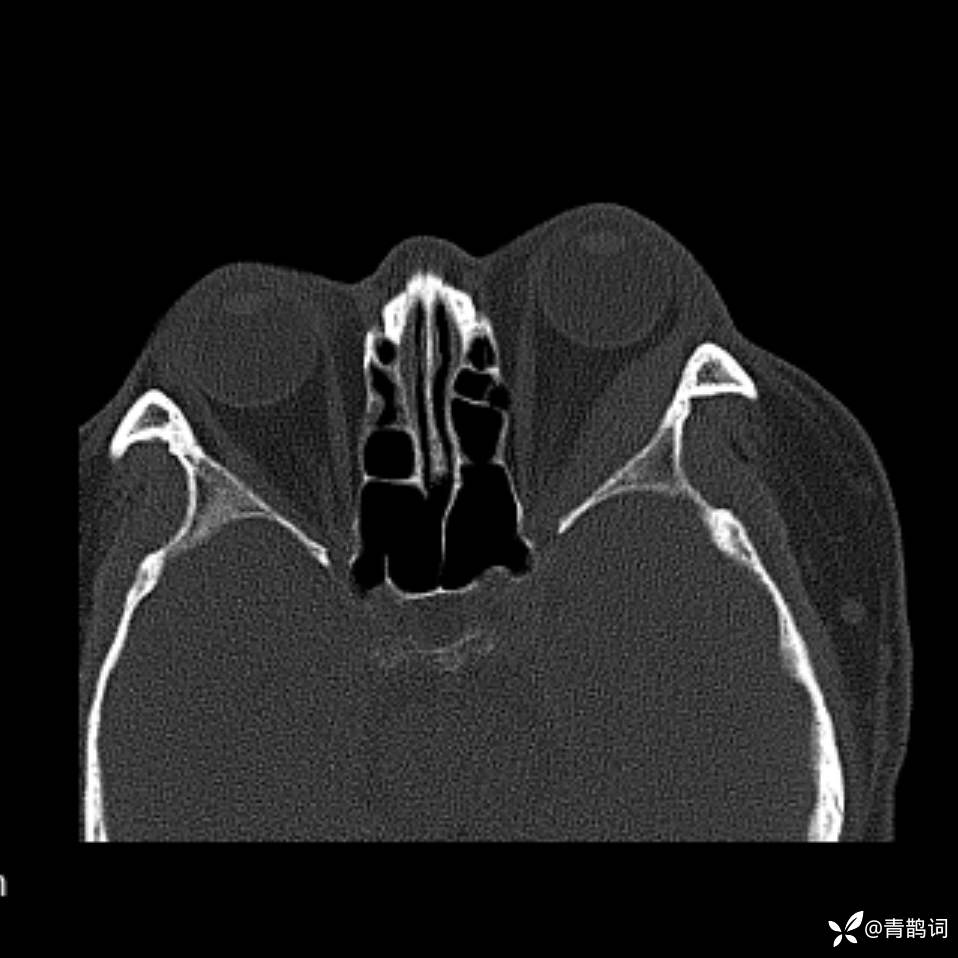

患者年龄:30岁。

患者性别:男。

简要病史:左颜面部肿胀2年,反复咳嗽咳痰,逐渐加重。

结合病史及影像学表现,期待评论区各位老师各抒己见~